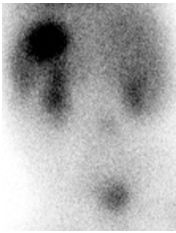

50. 一個6個月大男嬰,無特殊過去史,突然連續數天排出暗紅色血便,病嬰無其他臨床症狀。身體診察無特殊發現。下圖為病嬰Tc-99m核醫影像,顯示有病灶存在,下列敘述有誤? (A)此病因可能導致intussusception。 (B)此病因可能導致appendicitis。 (C)此病因可能導致peritonitis。 (D)常發生在1至2歲幼童。 (E)用內科方式即可治療此症。